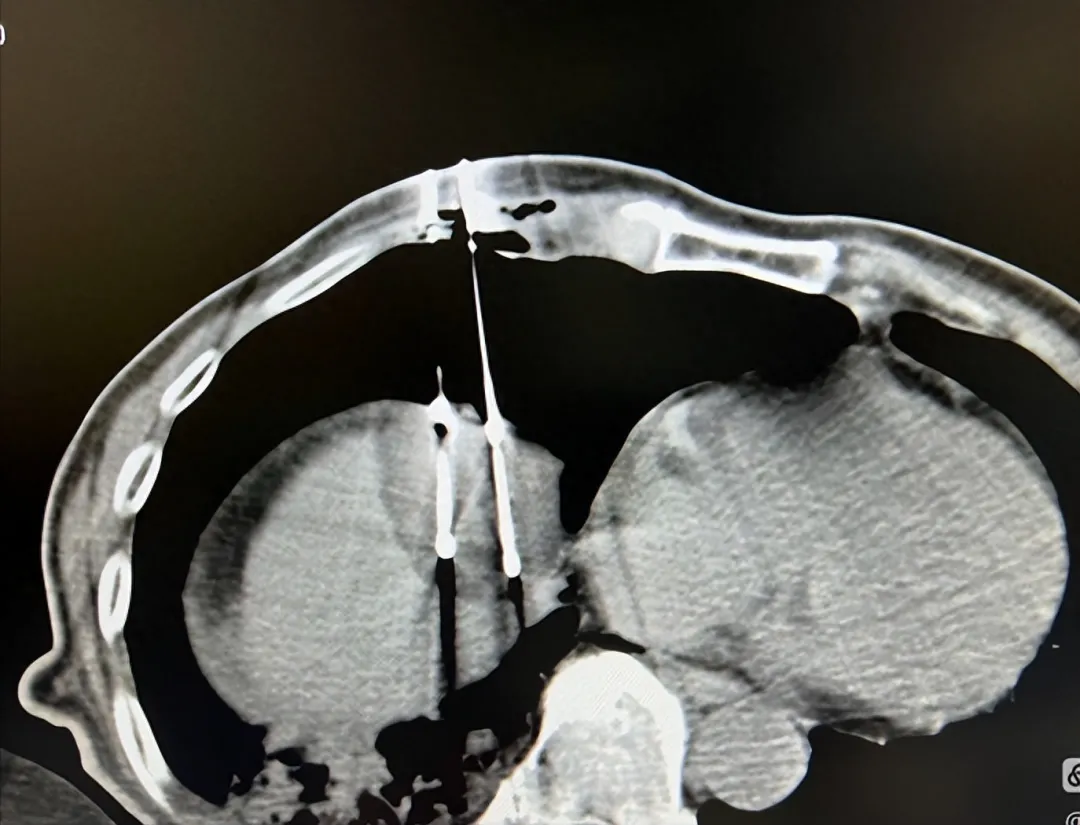

传统采用一根或两根穿刺针的方法直接建立人工气胸,容易造成肺损伤,而且术后排气也面临着一定困难。日本国立癌症中心小泽教授团队曾应用了一种创新性人工气胸技术——肝导向入路seldinger技术。

该技术在肝膈顶肿瘤、纵膈肿瘤及肾和肾上腺肿瘤的穿刺消融和活检手术中,技术成功率100%,副作用小,特别是避免了肺损伤。我曾采用此技术,建立人工气胸和人工胸水大约做了数十例手术,全部成功,效果不错。

注入500ml气体(最好是CO2),建立人工气胸将肺与膈肌分离开;

冷冻消融清晰显示足够的消融范围;

通过导管抽出气体,肺复张,人工气胸消除;

▲利用肝导向入路seldinger技术,在人工气胸下行膈顶肝癌冷冻消融术。